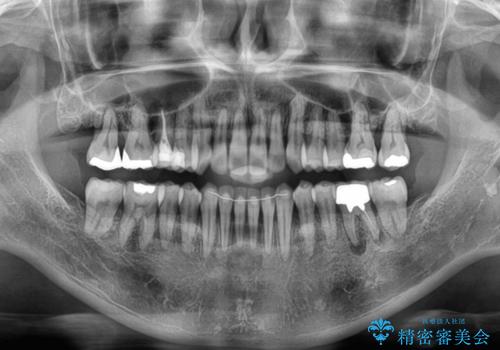

受け口傾向の骨格であり、前歯はクロスバイトまたは切端咬合となっており、下顎を中心に歯列全体の後方移動を行い、IPR(歯と歯の間を削る)によってデコボコが解消するように設計し、インビザラインにより治療を行うこととしました。